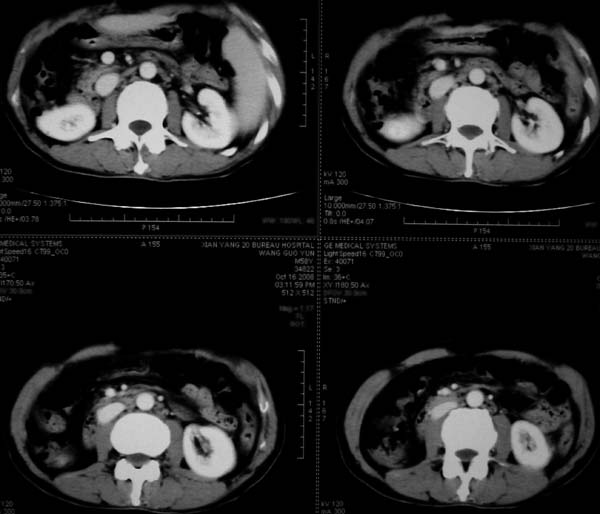

标题: CT16292:男,53岁,上腹部不适2月,B超发现肝内占位病变。 [打印本页]

标题: CT16292:男,53岁,上腹部不适2月,B超发现肝内占位病变。

符合肝ca增强,\"快进快出\";肝叶比例失常,右叶萎缩,肝裂增宽,脾大,肝硬化可能.

支持结节型肝癌。肝硬化脾大,病人是不是做过手术。

肝硬、脾大,右肾在稍息,考虑结节型肝癌可能,不排除血管瘤。

肝叶比例失调,左叶增大,肝裂增宽,脾脏增大,门脉增宽,肝右叶包膜下多发结节样阴影,增强虽说强化幅度不大,但还是符合快进快出特点;考虑肝硬化、脾大、结节型肝癌。胆管细胞癌多有延时强化、肝包膜凹陷征、周围胆管扩张等特点,本例明显不符;故不考虑。

动脉期静脉有显影 是否静脉有受侵改变啊